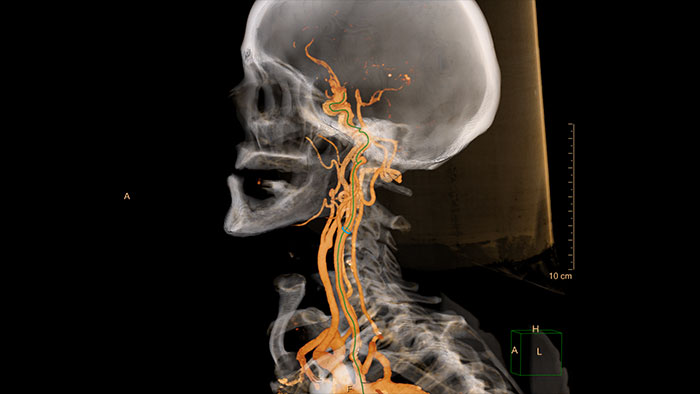

Comprehensive vascular analysis planning

Designed to examine and quantify different types of vascular lesions from CTA and MRA scans. It accommodates different modes of inspection, allows labeling different vascular lesions, and helps navigating through multiple findings. Demonstrated to reduce the post-processing time by 50% when compared to manual Head & Neck CT angiography (CTA) analysis*.

Benefits

* Ardley N et al. Efficacy of a new post processing workflow for CTA head and neck. ECR 2013 / C-1760.

Contrast arterial structures with surrounding bone and soft tissue to assist in identification of vascular abnormalities